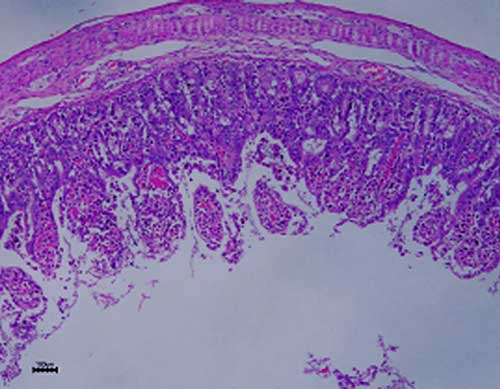

TGEV is a common cause of diarrhea in pigs, affecting all ages but significant deaths only occur in suckling pigs, with the severity related to the age of the animals infected. Almost all susceptible piglets under 10 days of age die within few days of exposure, but the mortality decreases the older they become. Only mild signs such as vomiting, regurgitation and agalactia are present in the lactating dams. In an endemic situation, namely, in vaccinated animals and/or where the acute wave has faded, sporadic diarrhea in older animals and post-weaning animals in contaminated nurseries are the spare clinical evidences of TGEV infection. As a member of the coronavirus group, TGEV is primarily an enteric virus, destroying enterocytes of the small intestine (Fig. 1), causing villous atrophy. Extra-intestinal sites of virus multiplication include the respiratory tract and mammary tissues (3,4,5), but the virus is most readily isolated from the intestinal tract and feces.

Villous atrophy was noted, suggesting an acute enterovirus infection (Fig. 1). Massive infiltration of inflammatory cellular components, vacuolization of enterocytes and destructive process were all sequelae of the ongoing infection.

Figure 1. Villous atrophy and vacuolization of enterocytes with a massive infiltration of inflammatory cellular components.

The typical findings of villous atrophy (Figure 1) and lymphopenia (Table 2), pointed toward a probable viral (acute) attack. The clinical manifestations especially the age distribution of the diseased animals at risk, the rapid spread of the disease among the pigsties, its high mortality rate, the antigenic ELISA positive reaction in 63% of the fecal samples submitted to KVI and the confirmations tests from the IZS, lead us to the conclusion that TGEV is responsible for this episode.